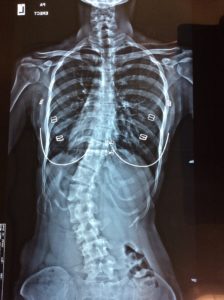

- Moderate: Patients with an angle between 25 degrees and 50 degrees need to wear a brace so that the angle does not deteriorate too quickly. Generally, doctors recommend wearing a brace for children who have not reached the angle that requires surgery (above 40 degrees) or are growing up. Research literature shows that although the scoliotic spine cannot be straightened back, the operation can be avoided or the operation can be delayed as long as one time (for growing children, it is necessary to adjust the screw every six months until the development is completed).

Due to differences in the angle, position, skeletal development and individual neuromusculoskeletal system, individualized/tailored treatment strategies are required, including: the style of the schoolbag, the posture of sitting, which exercise method can avoid or delay the operation, and Studies have shown that scoliosis is no longer just a problem with the "bone and muscle" system, but a problem with the "neuromusculoskeletal" system, so the "nervous/nerves" aspect must also be treated.